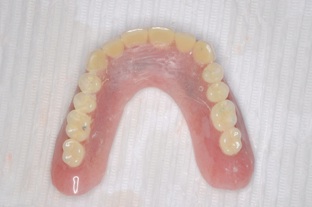

この方は結局、all on 4 を応用し、奥歯に両側2本のインプラントを傾斜埋入して、それにマグネットをつけました。これなら骨移植をせずにインプラントが可能になり、3ヶ月ほどで終了できます。

マグネットをつけているので大幅に義歯の面積を縮小することが可能になりました。